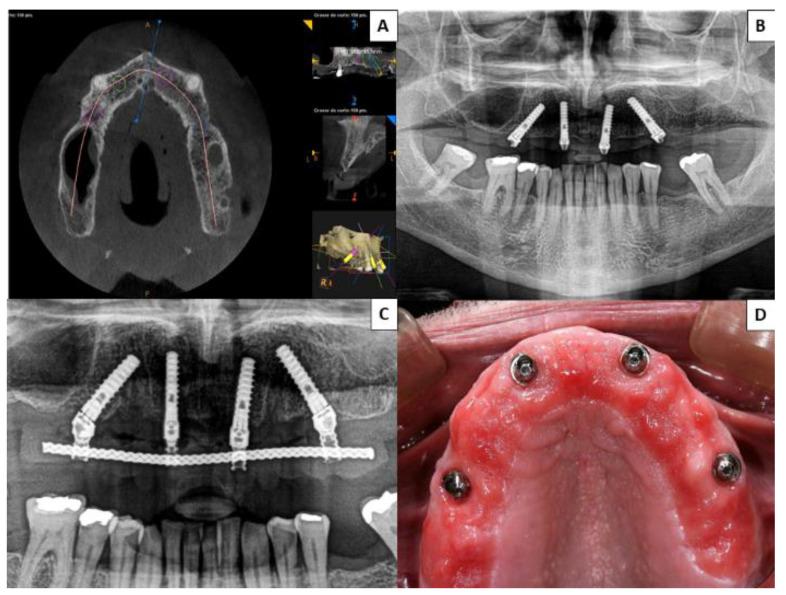

: No published research has compared patients' quality of life and satisfaction with fixed prostheses supported by zygomatic implants with those supported by all-on-four prostheses. The aim of this study was to evaluate patients' quality of life and satisfaction with fixed prostheses on zygomatic implants compared with the all-on-four concept. : A total of 80 patients with atrophic edentulous maxillae were randomized into two groups: Group 1 (rehabilitated with fixed prostheses supported by 2-4 zygomatic and 2-4 conventional implants in the anterior region) and Group 2 (fixed prostheses on four implants in the anterior region following an all-on-four concept). One year after placement of the definitive prostheses, patients completed OHIP-14 and satisfaction questionnaires. : In all seven domains of the OHIP-14 and in the overall scores, a worse quality of life was found in Group 2 patients, with statistically significant differences between the two groups ( ≤ 0.05). Patients with zygomatic implants were more satisfied with their prostheses, with a statistically significant difference ( < 0.001). : According to the results of this study, rehabilitation of patients with edentulous atrophic maxillae with prostheses supported by zygomatic implants combined with anterior implants provided better patient quality of life and satisfaction than prostheses supported by four implants.